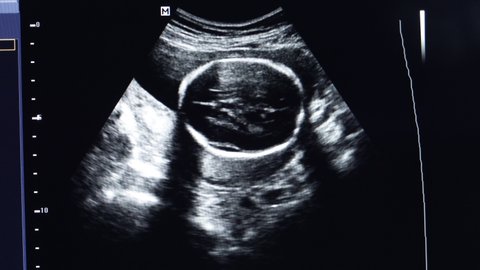

The ultrasound technician will measure the size of the babys head circumference abdominal circumference femur length and the diameter of the fetal skull. A head ultrasound is a scan through babys fontanelle soft spot in babys skull to examine the structures of the brain. I just want my baby to be OK I repeated over and over again on a Thursday morning last April.

This is the diameter between the two sides of the head and is measured after 13 weeks. The head ultrasound will be done in the radiology department of a hospital or in a radiology center. According to the Fetal Medicine Foundation your baby having a bigger than average head also called macrocephaly is actually pretty common impacting one in 100 babies.

This calculator shows if your babys head circumference is growing and progressing at a healthy rate. I just got my 28 week ultrasound results and am very concerned. The head circumference is usually done after 13 weeks of the pregnancy.